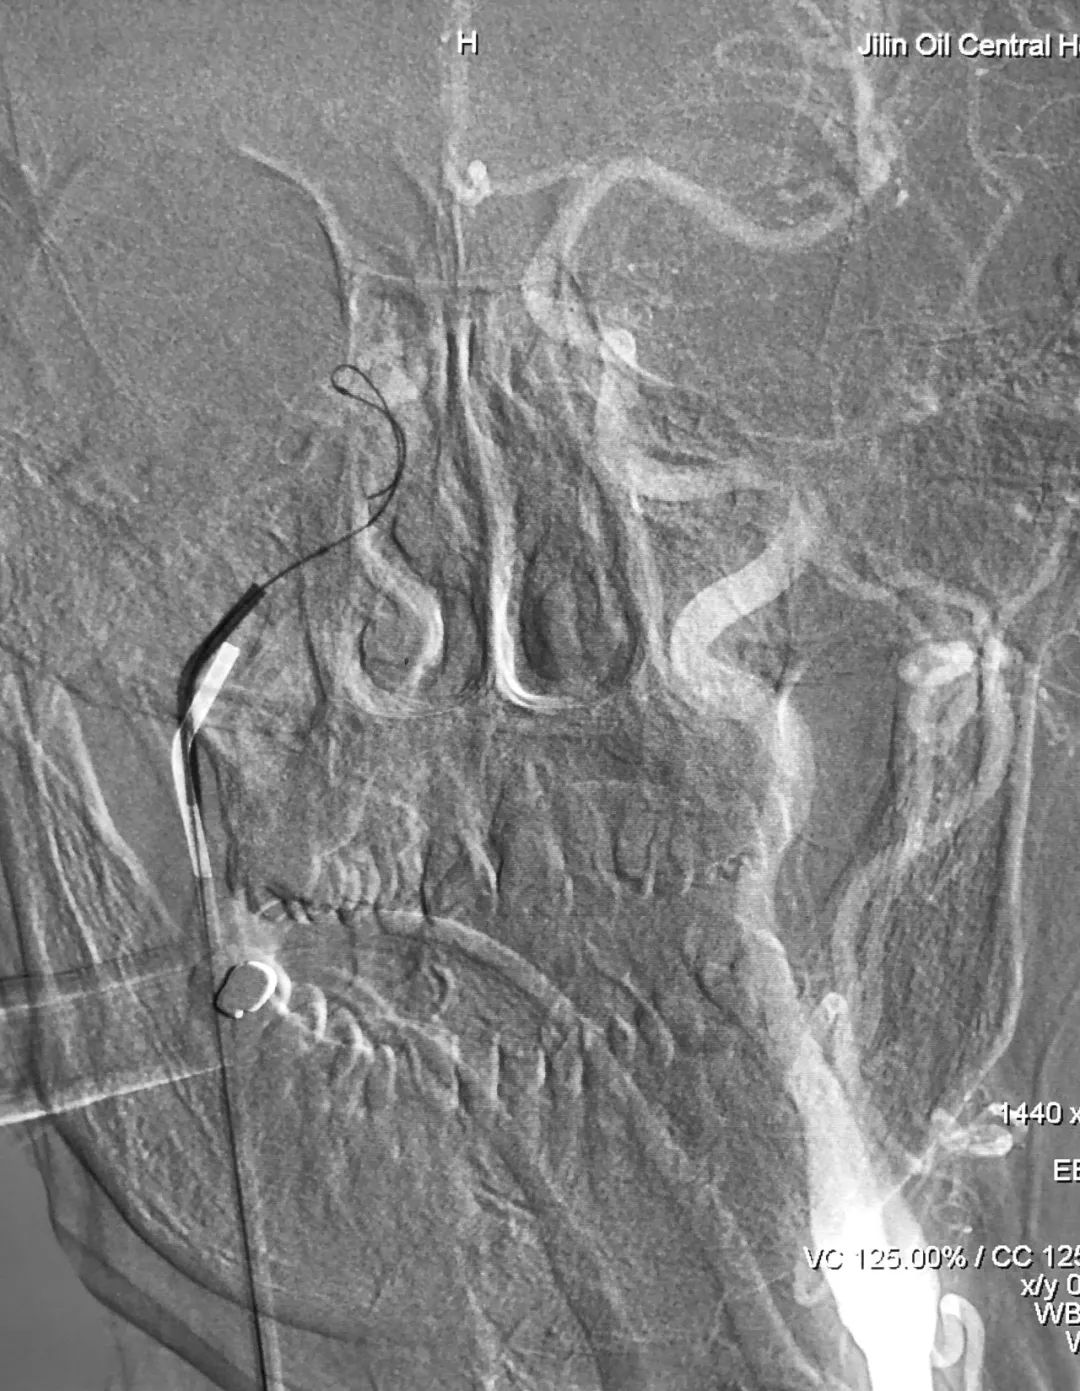

① 右侧股静脉穿刺置入6F鞘,左侧股动脉穿刺置入5F鞘。5F造影管由左侧股动脉进入,置于左侧颈总动脉,以备术中路图和造影;6F Envoy导引导管(红箭头)在泥鳅导丝引导下经右侧股静脉进入,置于右侧颈内静脉末端,因导引导管支撑力不足,管头在粗大的颈内静脉内摆动,泥鳅导丝无法将管头带入右侧岩下窦。在左侧颈总动脉路图指示下,经6F导引导管送入Echelon-10微导管+Sychro-14微导丝(蓝箭头),拟利用微导管超选右侧岩下窦,但仍因导引导管的支撑力不足,屡试屡败:

② 撤出6F Envoy导引导管,换用5F单弯造影管(强生),在泥鳅导丝引导下轻松对接右侧岩下窦,此处利用了强生单弯造影管强硬的支撑力和单弯的指向。在左侧颈总动脉正位路图指示下,Echelon-10微导管+Synchro-14微导丝经造影管送入右侧岩下窦,并长驱直入右侧海绵窦: